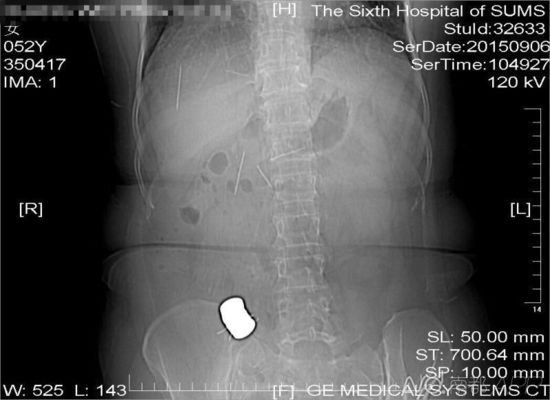

����CT�z��Y(ji��)�����@ʾ�����˸����ж���(g��)���ٮ����ɢ����C���

�����M(j��n)�е�CT�z��Y(ji��)���@ʾ���S�̸����ж���(g��)���ٮ����ɢ����C��ᘡ������t(y��)���S����ʿ��B���@Щᘷքeλ���S��С�c��(n��i)�������ѽ�(j��ng)����С�cɢ���ڸ�ǻ��(n��i)��߀�в��ֽ��ٮ������һ�K�ϸ����˔�(sh��)����ᘣ���һ�����M(j��n)�����٣�ʣ�µ�һ���ڼ���������ÿö�s�L4���ס�